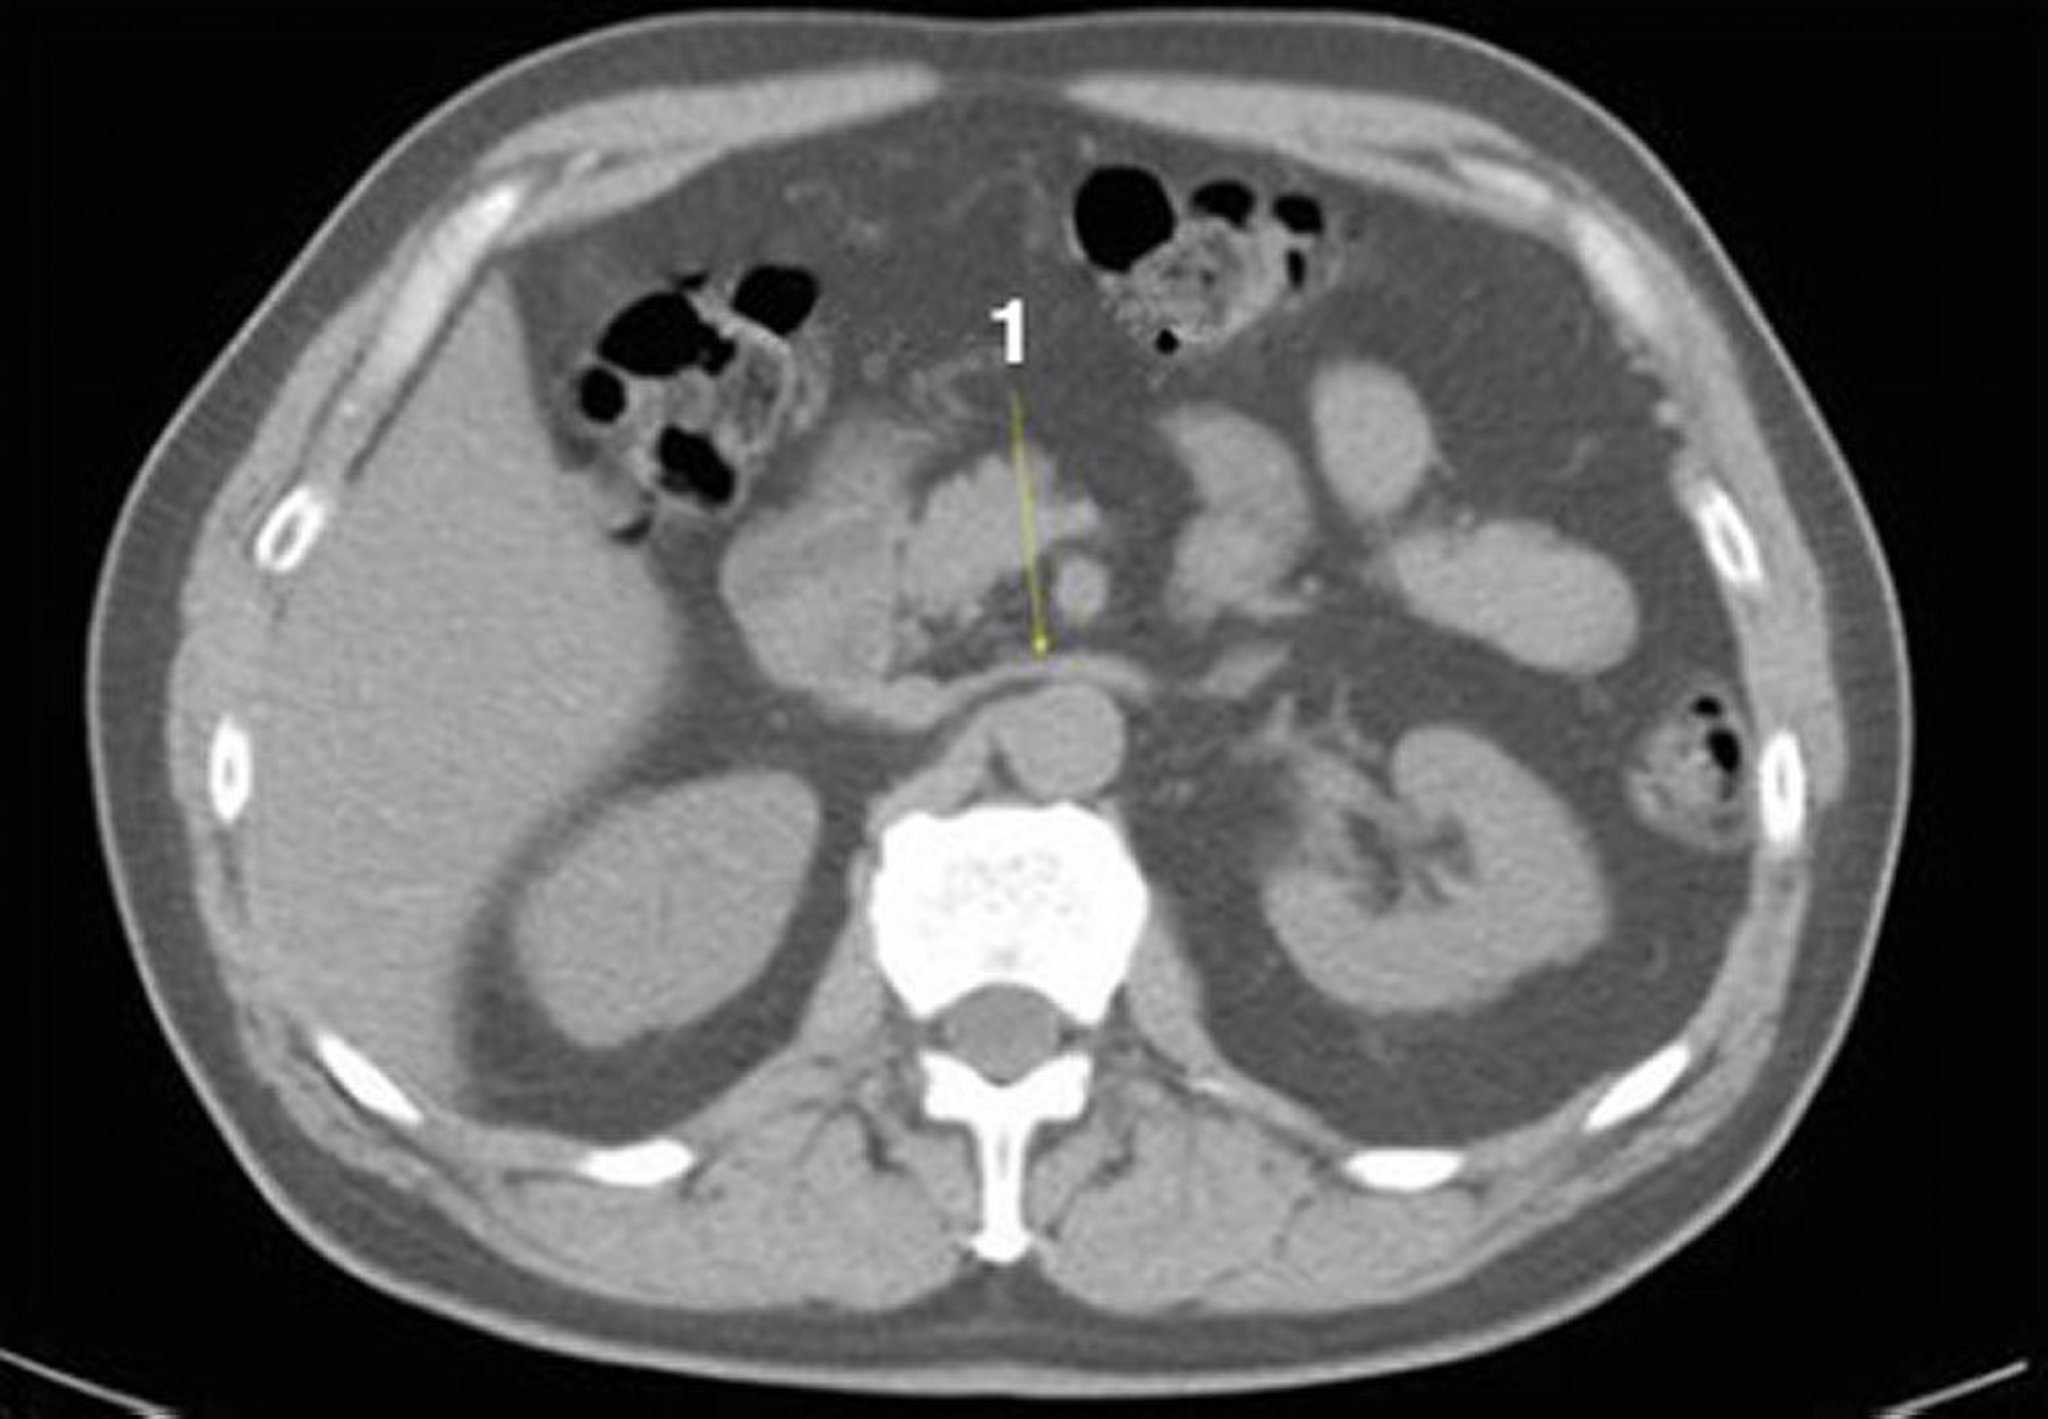

TC sem contraste do abdome e da pelve mostrando anatomia normal (lâmina 12)

1 = veia renal esquerda.